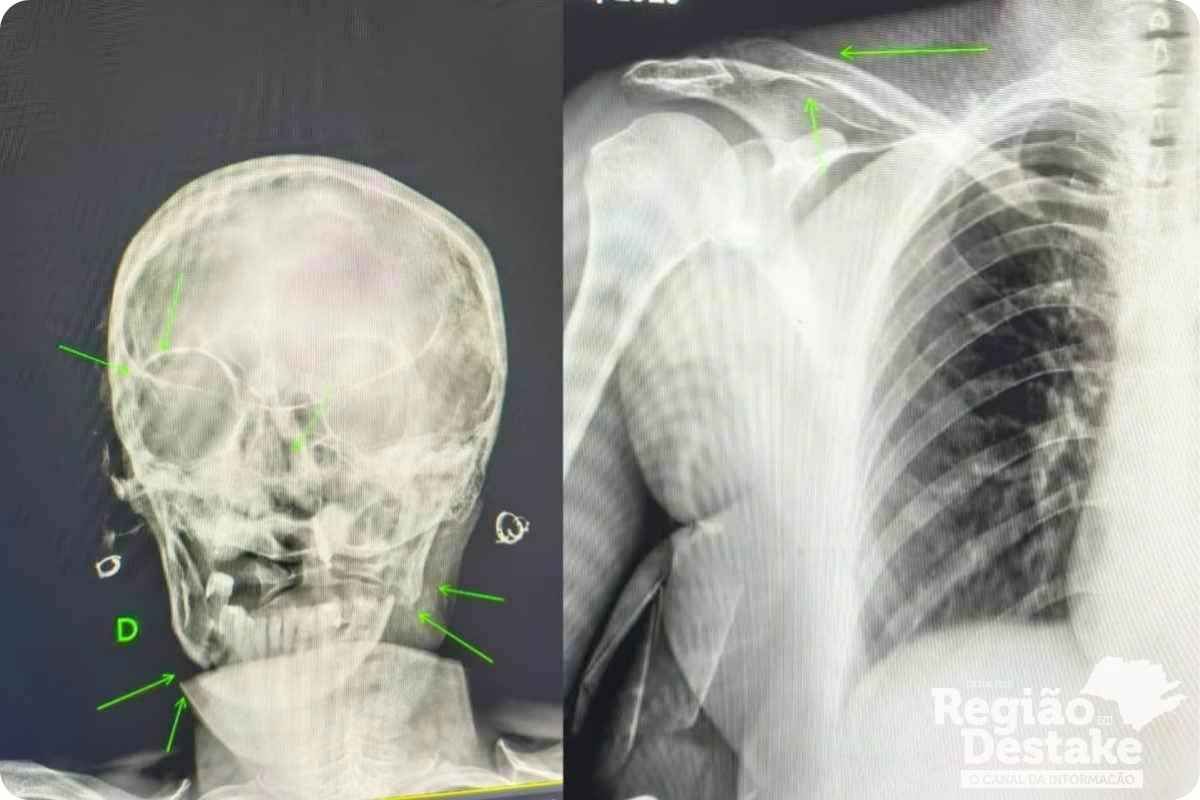

A vítima foi encaminhada inicialmente ao Hospital Municipal e, devido à gravidade do seu quadro clínico, precisou ser transferida para a UTI da Santa Casa de São Carlos. O caso segue sob apuração das autoridades competentes.